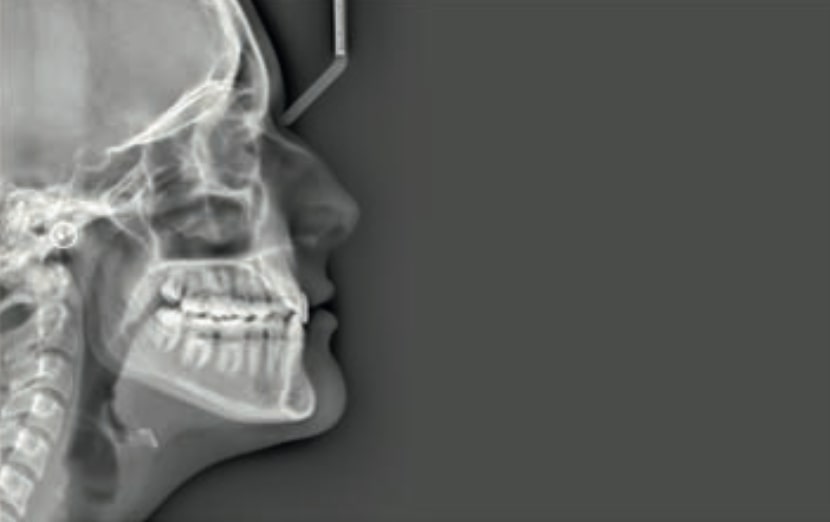

Chief complaint: The patient, a 19-year-old woman, was evaluated to undergo orthodontic treatment using the Angel Aligner Pro system. She presents with a skeletal Class III, mesofacial, with a dental Class III malocclusion and a 2 mm deviation of the lower midline to the left. Teeth 33 and 43 are out of the arch and cortical bone, with a crossbite issue on tooth 33. Fortunately, no functional issues affecting swallowing or breathing have been detected. The patient’s motivation for starting treatment was a general review of her dental and aesthetic health. The soft tissue analysis reveals mandibular protrusion that influences her facial profile. This diagnosis highlights the need for a comprehensive approach to address dental and skeletal misalignments, improving both the patient’s functionality and facial aesthetics.

• Soft Tissue Analysis: Jaw protrusion

Treatment plan